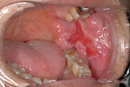

口腔がんの初期症状には、頬の内側にしこりや膨らみが現れることがあります。これに加えて、口内の粘膜が白く変色したり、出血することもあります。痛みが伴わないことが多いのも特徴です。早期発見が治療の成功に直結するため、これらの症状に気づいた際は早期に専門医を受診することが推奨されます。

口腔がんの最も一般的な初期症状の一つが、頬の内側や歯茎、舌などに現れるしこりや膨らみです。これらは、触ると硬く、痛みがないことが多いです。膨らみがしばらく治らず、何か異常がある場合は、がんの疑いが生じます。

2. 口内の粘膜の色の変化

口の中の粘膜が白くなったり、赤く変色することも口腔がんの兆候となり得ます。特に白斑(ホワイトスポット)や赤斑(エリテマ)などは、がんの前兆とされることがあるため、異常を感じたらすぐに確認しておくことが重要です。